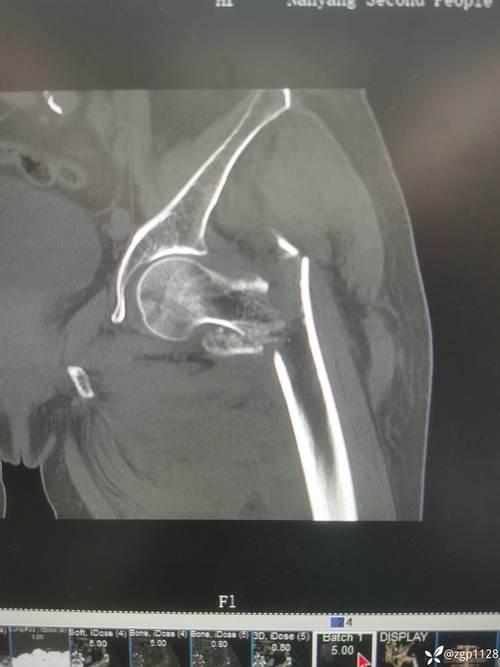

- 病例分析:如“患者,男,65岁,摔伤致右髋部疼痛、活动受限,X线示右股骨颈骨折,分型为Garden III型,请制定治疗方案并说明理由”,需涵盖分型依据(如Garden分型基于骨折移位程度)、手术方式选择(关节置换 vs. 内固定)、术后康复计划等。